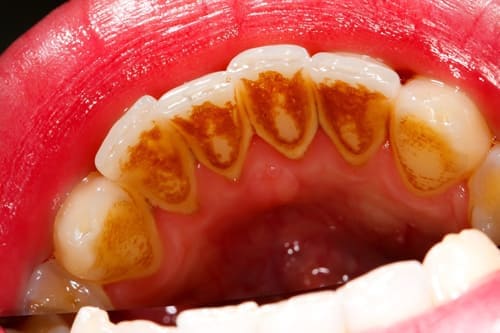

当院でスケーリングに使用している口腔機能殺菌水は、治療に使用することで徹底的な除菌を目指します。

この口腔機能殺菌水を使用し、歯の表面だけでなく、歯肉の内部にまで入り込んでいる歯垢や歯石を徹底的に除去することを目指します。

この治療は、歯周病の初期であれば1~2回です。中程度の方では2回ないし3回で終わります。重症の方では5~6回かかります。

スケーリング前